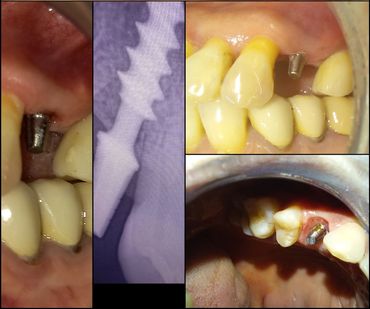

Un implant dentaire est une prothèse fixe utilisée pour remplacer la racine d'une dent manquante. Fabriqué généralement en titane, un matériau biocompatible, l'implant s’intègre naturellement à l’os de la mâchoire grâce à un processus appelé ostéointégration. Une fois l'implant en place, il sert de base solide pour une prothèse dentaire, telle qu'une couronne, un bridge ou une prothèse complète, afin de restaurer à la fois l'esthétique et la fonctionnalité de la dentition.

L’implant dentaire permet de remplacer une dent manquante de manière très esthétique avec un résultat très confortable car la dent est fixe et indépendante de ses voisines, comme une dent naturelle.

Parce qu’il sollicite l’os, l’implant résout tous les problèmes. Résistant et durable, il se substitue parfaitement à une racine naturelle dont il assume toutes les fonctions. Et la prothèse qu’il supporte, fabriquée sur mesure, s’intègre harmonieusement au reste de la dentition.

Prothèse sur implant